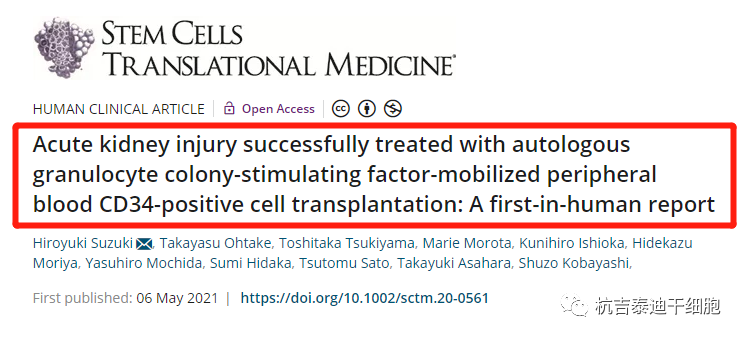

干細胞治療急性腎損傷的臨床案例

2021年9月13日,日本湘南鐮倉綜合醫院研究團隊在《干細胞轉化醫學》上發表文章,分享了利用自體干細胞移植成功治療急性腎損傷患者的經驗。干細胞移植后腎功能得到長期改善,主要表現為血清肌酐水平的改善。該案例初步證實干細胞療法治療急性腎損傷安全有效。

研究團隊選取了一名36歲男性患者的嚴重急性腎損傷(AKI),他被診斷為難治性高血壓、視網膜,心臟和腦損害,以及嚴重的腎功能不全。經血液透析后血肌酐水平仍然很高,因此接受了干細胞治療。